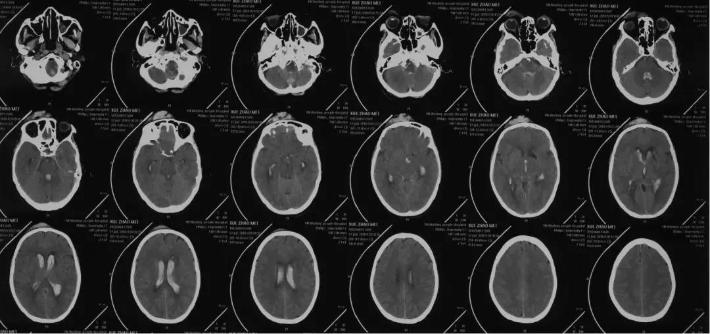

当地医院头颅CT

当地医院胸部CT